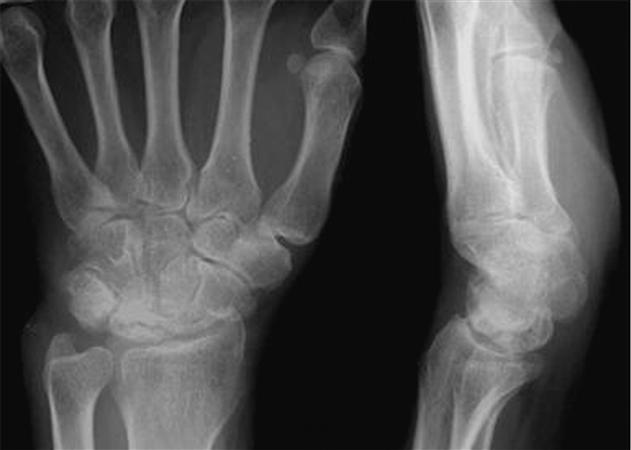

Stage III 부터는 주상골도 영향을 받기 시작하며 회전을 하거나(IIIA, cortical ring 관찰가능), carpal height 가 줄어드는 것을 확인할 수 있습니다. (IIIB), IIIA 까지는 II와 치료를 거의 동일하게 하지만, IIIB 부터는 Proximal row carpectomy 나 STT, SC fusion 등을 시행해 볼 수 있습니다.